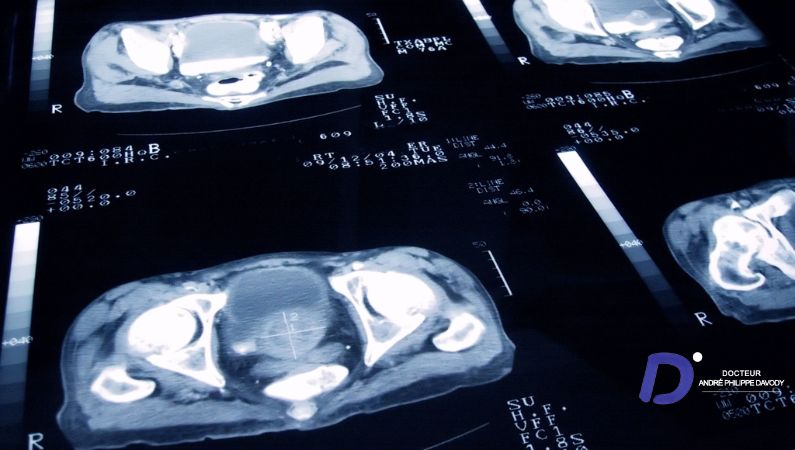

Un cancer de prostate oligométastatique définit un cancer prostatique qui présente un nombre limité de localisations secondaires (métastases). Ce stade est de plus en plus couramment identifié, notamment grâce aux progrès technologiques de l’imagerie médicale et à l’utilisation de nouveaux produits de contraste (comme la Choline, utilisée lors d’un TEP-scan).